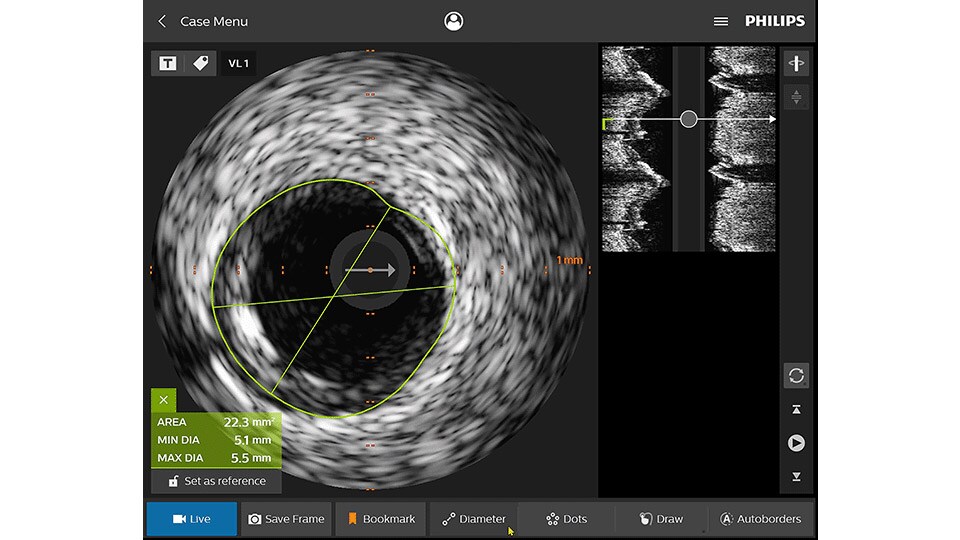

IVUS

Intravascular ultrasound (IVUS) provides images from within the vessel to accurately assess and optimize your treatment plan.